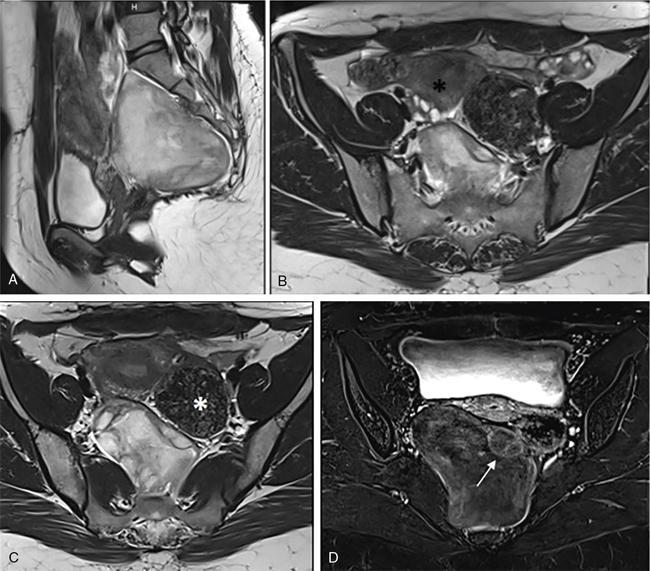

Suriyaprakash Nagarajan, Rupa Renganathan, Suhasini Balasubramaniam, Anupama Chandrasekharan, Kumarsampath Sumeena OVARIAN CYST VERSUS BLADDER Cystic lesions are common in female pelvis and mostly they originate from ovary. Ovarian cysts can arise from epithelial, stromal or germ cell components and can be benign or malignant cystic lesions. Pelvic Ultrasonography (USG) is the preferred imaging modality for evaluation of adnexal cystic lesions. Large simple ovarian cyst appears unilocular, anechoic with thin smooth walls. Such large simple cysts are confused with distended bladder. Distended bladder is a condition in which the urinary bladder is full and the patient is unable to void completely causing abdominal discomfort and pain. Distended bladder can be due to obstruction to passage of urine, neurological disorder or spastic sphincter. Differential diagnosis of cystic lesions in pelvis can be intraperitoneal, extraperitoneal and both intraperitoneal and extraperitoneal. Cystic lesions of intraperitoneal origin includes peritoneal inclusion cyst, paraovarian cyst, mucocele of appendix and hydrosalpinx. It is important to differentiate large simple ovarian cyst and distended bladder when patient presents with lower abdomen pain and the patient’s clinical history helps to make an accurate diagnosis (Table 11.4.1.1). UTERINE VERSUS EXTRAUTERINE MASS Ultrasound is usually the initial imaging modality for the pelvic mass. When USG findings are indeterminate to ascertain the organ of origin and to characterize, the next imaging modality is MRI due to its superior soft tissue resolution and multiplanar imaging capability (Figs. 11.4.2.1 and 11.4.2.2). Signs are demonstrated in Figs. 11.4.2.3 to 11.4.2.6. The sequences used in MRI pelvis are conventional T2WI in all three planes and T1WI in single plane. The problem-solving sequences are oblique coronal and oblique axial T2 along and perpendicular to the long axis of uterus in sagittal localizer. It can identify the organ of origin. Other sequences like T1 fat sat, diffusion-weighted imaging (DWI) and dynamic contrast T1WI with fat sat and subtracted images help to characterize the lesion further. BLADDER MASS VERSUS PROSTATE MASS Irregular mass lesions in the bladder neck are termed as ‘Bladder occupying lesions’. It is often difficult to determine whether the origin of these lesions is the bladder or the prostate gland. Transabdominal Ultrasound with colour Doppler studies and CT imaging do not usually delineate the origin of the lesions. The following features may aid in the differentiation (Table 11.4.3.1): History Painless haematuria Usually asymptomatic Investigations TAS, TRUS, MRI, Cystoscopy-guided biopsy PSA, DRE, TRUS, MRI, TRUS-guided biopsy At what point is the cross over between the two lesions T4 bladder cancer invading the prostate Aggressive prostate cancer protruding into the bladder Epicenter of the lesion Within the bladder Within the prostate gland Central necrosis in the mass Not commonly seen Seen in sarcomas IVU/CT urography Additional lesions in the urinary tract suggest that the bladder occupying mass in the bladder neck is of bladder-origin Prostate masses do not commonly cause masses in the urinary tract except for the very rare metastasis Virtual cystoscopy Additional lesions in the bladder wall and dome suggest that the bladder occupying mass in the bladder neck is of bladder-origin MRI T2 hypointensity Bladder masses are usually T2 hyperintense Seen in adenocarcinomas MRI T2 hyperintensity Bladder masses are usually T2 hyperintense Urothelial tumours infiltrating the prostate, neuroendocrine masses MRI T1 and T2 hyperintensity Bladder masses are usually T1 hypointense and T2 hyperintense Mucinous adenocarcinoma MRS Elevated choline values are seen in highly cellular masses Elevated choline:citrate ratio in prostate malignancies No significant finding in mucinous adenocarcinoma DWI Diffusion restriction is seen in malignant bladder masses No restriction in mucinous adenocarcinoma BPH versus bladder mass Exophytic BPH has signal intensities and appearance similar to and is contiguous with BPH within the gland OVARIAN MASS VERSUS PARAOVARIAN MASS Ultrasonography (USG) is the primary imaging modality in patients presenting with pelvic symptoms. Transvaginal, transabdominal or both should be performed in evaluation of such patients to differentiate ovarian and nonovarian origin of the lesions. Ovarian lesions can be a simple ovarian cyst, complex cyst with septations and solid components or a solid mass. Paraovarian lesions are remnants of the Wolffian duct in the mesosalpinx along fallopian tube or the ovaries and do not arise from the ovary. Paraovarian cysts are classified based on their site of origin into paratubal mesosalpingeal cysts, hydatid cysts of Morgagni, paraovarian cystadenoma and subserosal cysts. Differentiation of ovarian and paraovarian lesion poses significant diagnostic challenge. Both Computed tomography (CT) and Magnetic resonance imaging (MRI) are essential problem-solving tool in determining the site of origin of a pelvic mass. The first step in pelvic mass evaluation is to find out if it is ovarian or nonovarian in origin. Characterization of paraovarian or ovarian lesions is of utmost importance in order to optimize therapeutic procedures and it influences patients management (Figs. 11.4.4.1 and 11.4.4.2). Findings such as ovarian vascular pedicle sign, claw sign, bird beak sign and visualization of normal ovary helps to differentiate between ovarian and paraovarian lesions. Subsequently ovarian lesions should be categorized into benign, indeterminate and malignant masses (Table 11.4.4.1).

Ipsilateral ovary not seen separately from the lesion (Phantom sign) or the cyst is seen to arise from within the ovary (embedded organ sign).

Complete or incomplete septae often seen (Fig. 11.4.1.2A).

Ovarian cysts are anechoic lesions noted on one side of pelvis (Fig. 11.4.1.2B). Normal ovarian stroma can be seen around the cysts in case of small cysts.

Colour Doppler shows vascularity in the septum (Fig. 11.4.1.2C).

Solid components more commonly seen (Fig. 11.4.1.2D).